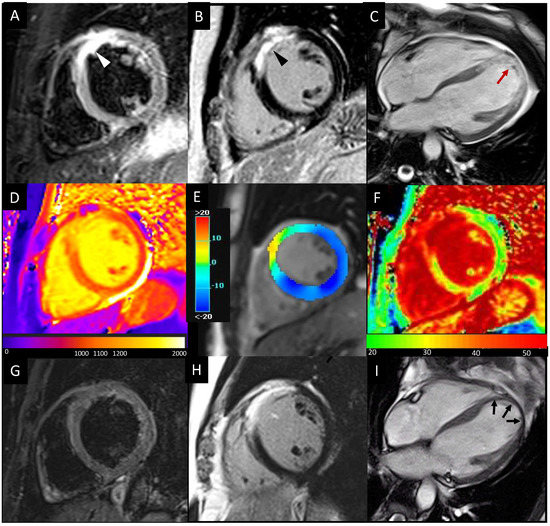

- Scatteia, A.; Baritussio, A.; Bucciarelli-Ducci, C. Strain imaging using cardiac magnetic resonance. Heart Fail. Rev. 2017, 22, 465–476. [Google Scholar] [CrossRef]

- Pedrizzetti, G.; Claus, P.; Kilner, P.J.; Nagel, E. Principles of cardiovascular magnetic resonance feature tracking and echocardiographic speckle tracking for informed clinical use. J. Cardiovasc. Magn. Reson. 2016, 18, 51. [Google Scholar] [CrossRef]

- Garg, P.; Kidambi, A.; Swoboda, P.P.; Foley, J.R.; Musa, T.A.; Ripley, D.P.; Erhayiem, B.; Dobson, L.E.; McDiarmid, A.K.; Fent, G.J.; et al. The role of left ventricular deformation in the assessment of microvascular obstruction and intramyocardial haemorrhage. Int. J. Cardiovasc. Imaging 2017, 33, 361–370. [Google Scholar] [CrossRef] [PubMed]

- Ugander, M.; Bagi, P.S.; Oki, A.J.; Chen, B.; Hsu, L.Y.; Aletras, A.H.; Shah, S.; Greiser, A.; Kellman, P.; Arai, A.E. Myocardial edema as detected by pre-contrast T1 and T2 CMR delineates area at risk associated with acute myocardial infarction. JACC Cardiovasc. Imaging 2012, 5, 596–603. [Google Scholar] [CrossRef]

- Bulluck, H.; Hammond-Haley, M.; Fontana, M.; Knight, D.S.; Sirker, A.; Herrey, A.S.; Manisty, C.; Kellman, P.; Moon, J.C.; Hausenloy, D.J. Quantification of both the area-at-risk and acute myocardial infarct size in ST-segment elevation myocardial infarction using T1-mapping. J. Cardiovasc. Magn. Reson. 2017, 19, 57. [Google Scholar] [CrossRef]

- Dall’Armellina, E.; Piechnik, S.K.; Ferreira, V.M.; Si, Q.L.; Robson, M.D.; Francis, J.M.; Cuculi, F.; Kharbanda, R.K.; Banning, A.P.; Choudhury, R.P.; et al. Cardiovascular magnetic resonance by non contrast T1-mapping allows assessment of severity of injury in acute myocardial infarction. J. Cardiovasc. Magn. Reson. 2012, 14, 15. [Google Scholar] [CrossRef]

- Bulluck, H.; Rosmini, S.; Abdel-Gadir, A.; White, S.K.; Bhuva, A.N.; Treibel, T.A.; Fontana, M.; Gonzalez-Lopez, E.; Reant, P.; Ramlall, M.; et al. Automated Extracellular Volume Fraction Mapping Provides Insights Into the Pathophysiology of Left Ventricular Remodeling Post-Reperfused ST-Elevation Myocardial Infarction. J. Am. Heart Assoc. 2016, 5, e003555. [Google Scholar] [CrossRef]

- Garg, P.; Broadbent, D.A.; Swoboda, P.P.; Foley, J.R.J.; Fent, G.J.; Musa, T.A.; Ripley, D.P.; Erhayiem, B.; Dobson, L.E.; McDiarmid, A.K.; et al. Extra-cellular expansion in the normal, non-infarcted myocardium is associated with worsening of regional myocardial function after acute myocardial infarction. J. Cardiovasc. Magn. Reson. 2017, 19, 73. [Google Scholar] [CrossRef] [PubMed]

- Kidambi, A.; Motwani, M.; Uddin, A.; Ripley, D.P.; McDiarmid, A.K.; Swoboda, P.P.; Broadbent, D.A.; Musa, T.A.; Erhayiem, B.; Leader, J.; et al. Myocardial Extracellular Volume Estimation by CMR Predicts Functional Recovery Following Acute MI. JACC Cardiovasc. Imaging 2017, 10, 989–999. [Google Scholar] [CrossRef] [PubMed]